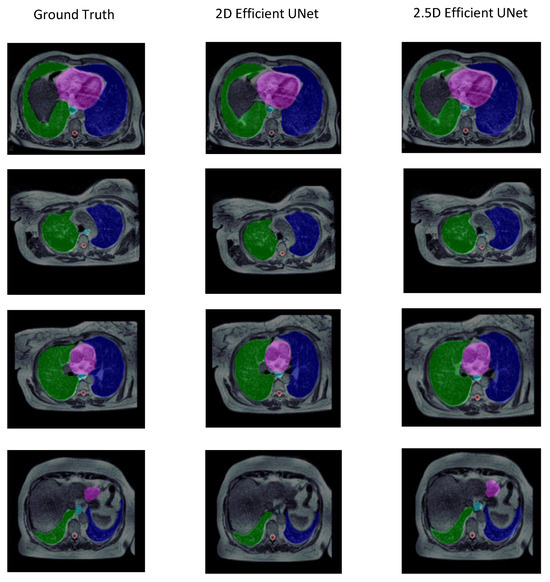

| Strategy | DSC | IoU | HD (mm) | Volume (Bland–Altman) | Volume (Correlation) |

|---|---|---|---|---|---|

| 2.5D | 0.820 ± 0.041 | 0.725 ± 0.052 | 10.353 ± 4.974 | 153.943 ± 50.149 | 0.734 ± 0.090 |

| 2D | 0.804 ± 0.058 | 0.711 ± 0.062 | 25.663 ± 18.724 | 151.915 ± 55.747 | 0.726 ± 0.073 |

| Organ | Strategy | Metrics | ||||

|---|---|---|---|---|---|---|

| IoU | DSC | HD (mm) | Volume | |||

| Bland-Altman | Correlation | |||||

| Left Lung | 2D | 0.895 ± 0.033 | 0.944 ± 0.018 | 14.492 ± 13.280 | 225.900 ± 101.430 | 0.978 ± 0.009 |

| 2.5D | 0.895 ± 0.031 | 0.944 ± 0.017 | 9.443 ± 1.953 | 216.580 ± 78.003 | 0.976 ± 0.008 | |

| Right Lung | 2D | 0.912 ± 0.011 | 0.953 ± 0.006 | 70.157 ± 43.920 | 209.380 ± 47.580 | 0.994 ± 0.001 |

| 2.5D | 0.904 ± 0.017 | 0.949 ± 0.009 | 9.739 ± 2.853 | 236.69 ± 69.311 | 0.992 ± 0.004 | |

| Heart | 2D | 0.860 ± 0.018 | 0.924 ± 0.010 | 19.403 ± 19.860 | 235.939 ± 108.410 | 0.983 ± 0.009 |

| 2.5D | 0.856 ± 0.037 | 0.922 ± 0.021 | 11.270 ± 8.454 | 237.638 ± 84.649 | 0.975 ± 0.018 | |

| Esophagus | 2D | 0.356 ± 0.116 | 0.513 ± 0.134 | 10.772 ± 5.280 | 74.510 ± 16.860 | 0.454 ± 0.205 |

| 2.5D | 0.384 ± 0.078 | 0.551 ± 0.080 | 11.710 ± 5.689 | 66.017 ± 13.650 | 0.422 ± 0.254 | |

| Spinal cord | 2D | 0.534 ± 0.133 | 0.685 ± 0.121 | 13.490 ± 11.250 | 13.835 ± 4.430 | 0.223 ± 0.138 |

| 2.5D | 0.585 ± 0.096 | 0.733 ± 0.077 | 9.600 ± 5.920 | 12.770 ± 5.130 | 0.304 ± 0.164 | |